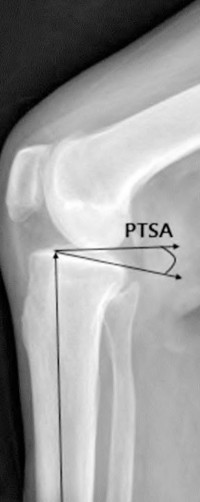

Question 61

During a standard Cruciate-Retaining (CR) Total Knee Arthroplasty, what is the primary consequence of an excessive posterior slope cut on the proximal tibia?

During a cruciate-retaining (CR) total knee arthroplasty trial, the knee is well-balanced in extension, but the anterior tibia lifts off the trial baseplate in deep flexion. What is the most likely cause?

Explanation